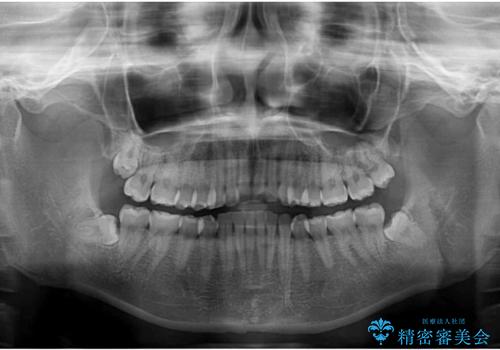

- 食いしばりが気になっていたとのことで来院された患者様です。

当初は睡眠時のマウスピースのみの製作をご希望でしたが、矯正治療の提案をしたところ、インビザラインにて矯正治療を行うこととなりました。

矯正治療中に食いしばりがより強くなることがあるため、半年に1回のペースでボツリヌストキシンによる咬合力緩和を並行して行うこととしました。